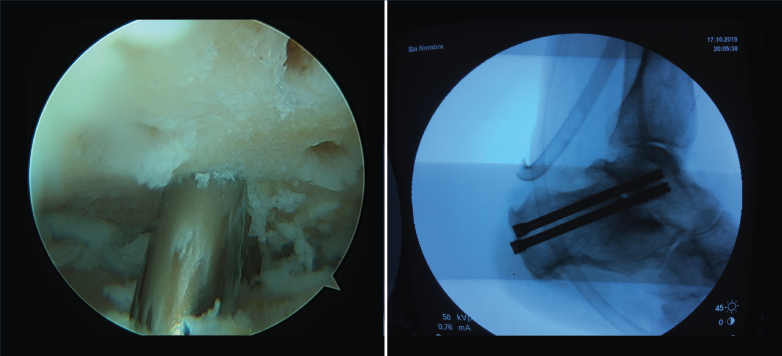

- Cirugía artroscópica: lesiones osteocondrales, tratamiento artroscópico de la inestabilidad (reparación y técnicas de reconstrucción), endoscopia posterior de tobillo y tendoscopia (Figuras 4, 5, 6 y 7).

Figura 7. Artrodesis subastragalina artroscópica.